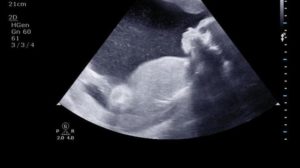

Последнее УЗИ во время беременности проводится в III триместре. Исследование назначается для получения оценки развития плода, а также для исключения каких-либо проблем с его здоровьем.

В ходе проведения манипуляции женщина может увидеть малыша, который уже полностью сформировался и уже похож на полноценного новорожденного младенца. Кроме этого, третье УЗИ помогает доктору выбрать оптимальный вариант родовспоможения.

Третье УЗИ несколько отличается от предыдущих двух исследований на раннем сроке. Отличие заключается только в технологии проведения: в 3 триместре диагностика проводится трансабдоминально, то есть через стенку брюшины.В III триместре ультразвук делают без наполнения мочевого пузыря, поскольку матка уже довольно большая и малыша хорошо видно.